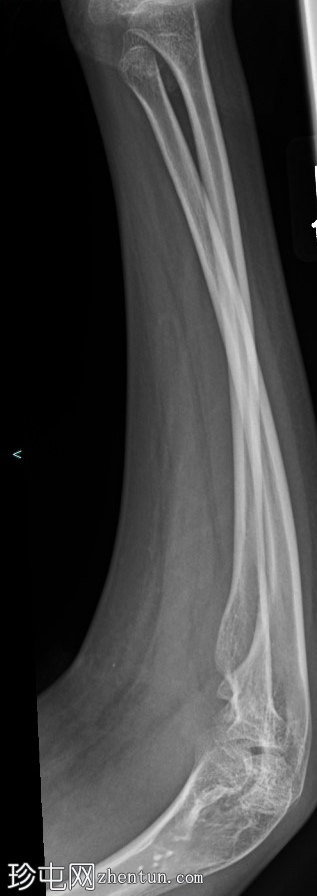

前臂X光片,2个视角 - 右侧

X光片

正面

右侧桡骨弯曲畸形,伴有骨骼发育不良,桡骨远端桡骨倾斜度(尺骨倾斜度)增大,尺骨变异为负值。

腕骨弧形完整,桡骨和尺骨之间无腕骨楔入征兆。

前臂无急性骨折。

周围软组织中度水肿。